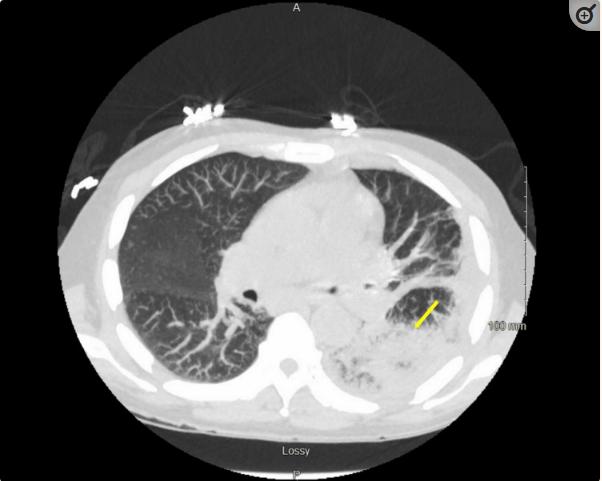

该患者最初的胸部CT检查与LLL肺炎有关,很可能是由于恶心和长期饮酒引起的误吸入。嘱进行感染性检查,并转为静脉注射哌拉西林/他唑巴坦(左辛)和应激剂量类固醇。入院两天后,患者对左侧局限性积液进行了诊断性胸腔穿刺,并清除了700cc化脓性液体。液体培养显示4+星形链球菌。细胞学检查恶性细胞阴性,但显示大量炎性细胞,这与脓胸一致。痰培养培养出正常的口腔菌群。胸部CT复查显示LLL广泛浑浊,有空洞区域,提示坏死性感染(图2)。

图2、胸部CT显示左下叶空洞性病变的浑浊和坏死